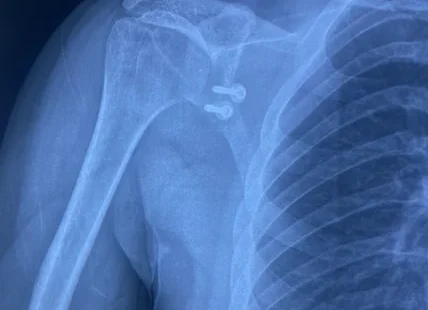

How are dislocated shoulders diagnosed?

Orthopaedic surgeon can easily diagnose a dislocated shoulder with a physical exam and few examination test in emergency room or clinic.

Investigations needed to diagnose and plan further management of shoulder dislocation.